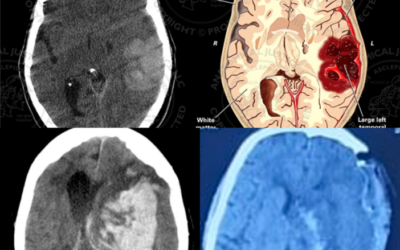

Decoding Brain Disorders: Causes, Symptoms and the Latest Treatment Options

Like a complex and intricate circuitry, humans have billions of neurons that connect up and control all functions of our body. It controls our thoughts, feelings and emotions, movements, memory, and their power to interact. Aside from allowing more...